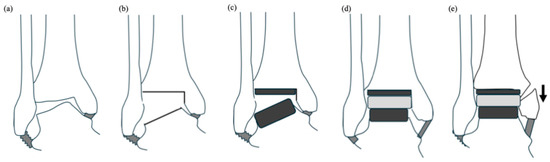

Figure 6.

Surgical sequence of total ankle arthroplasty by transfibular approach, using the TIBIA #2 technique. (a) Preoperative condition in varus-type ankle osteoarthritis. (b) Precutting of the lateral half of the distal tibial surface permits aligning the tibial shaft perpendicularly to the superior talar surface. (c) The periarticular bones on both the tibial and talar sides are simultaneously prepared for orthogonal implantation. (d) The components are implanted in situ. The thickness of the polyethylene insert is adjusted so that the medial ligament is appropriately tensioned. (e) When the osteotomized fibula is refixed, the position of the lateral malleolus is adjusted to optimize the congruity of the lateral gutter. The arrow indicates the fibular shortening.

15]. However, as the lateral approach utilized with the TM Ankle system involves fibular osteotomy (

Figure 6), the congruity of the lateral gutter can be optimized by adjusting the height of the lateral malleolus, specifically by shortening the fibular length during internal fixation of the osteotomy site.

Additionally, if soft tissue imbalance occurs after implantation due to the relative looseness of the lateral capsule compared to the contracted medial capsule, augmentation of the anterior talofibular ligament with an artificial ligament can be easily performed. These features may collectively enhance the deformity correction capability of the TM Ankle system [

16], while the TIBIA #2 technique appears to effectively address issues of bony conflict that challenge the realignment procedures necessary for orthogonal bone cutting. We believe that transfibular TAA using this technique has the potential to expand the indications for TAA to include ankles with severe preoperative varus deformities exceeding the 15-degree limit.